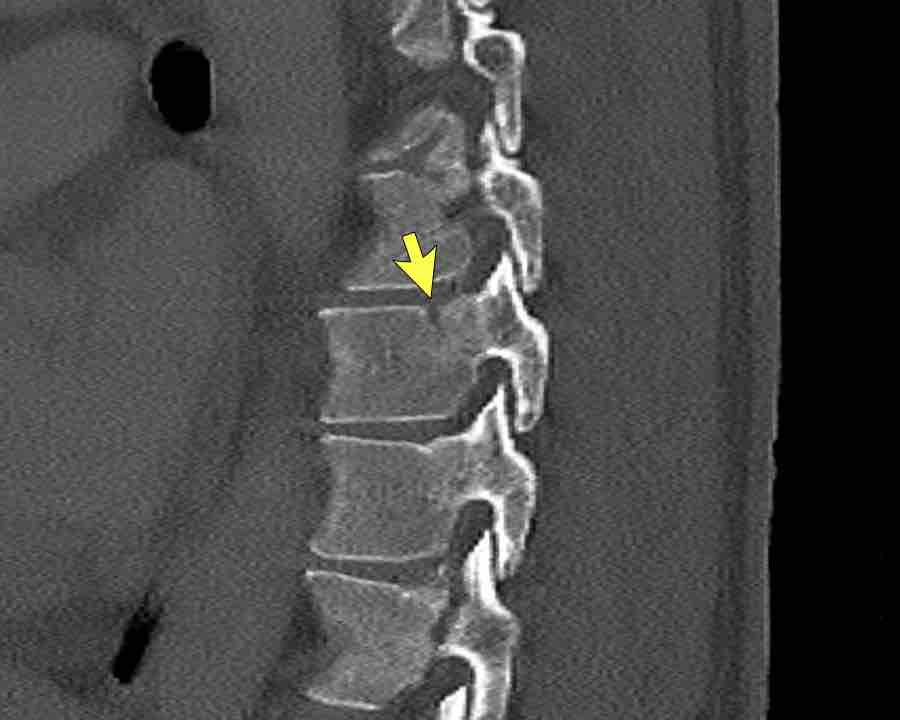

These images are of a young child with a spinal injury.

Findings

- Clear widening of the interspinous distance (yellow arrow)

- Black arrowhead: small avulsion fracture to the flexion distraction

- MRI better depicts the ligamentous injury, which was suspected on CT

Conclusion

Injury type B2